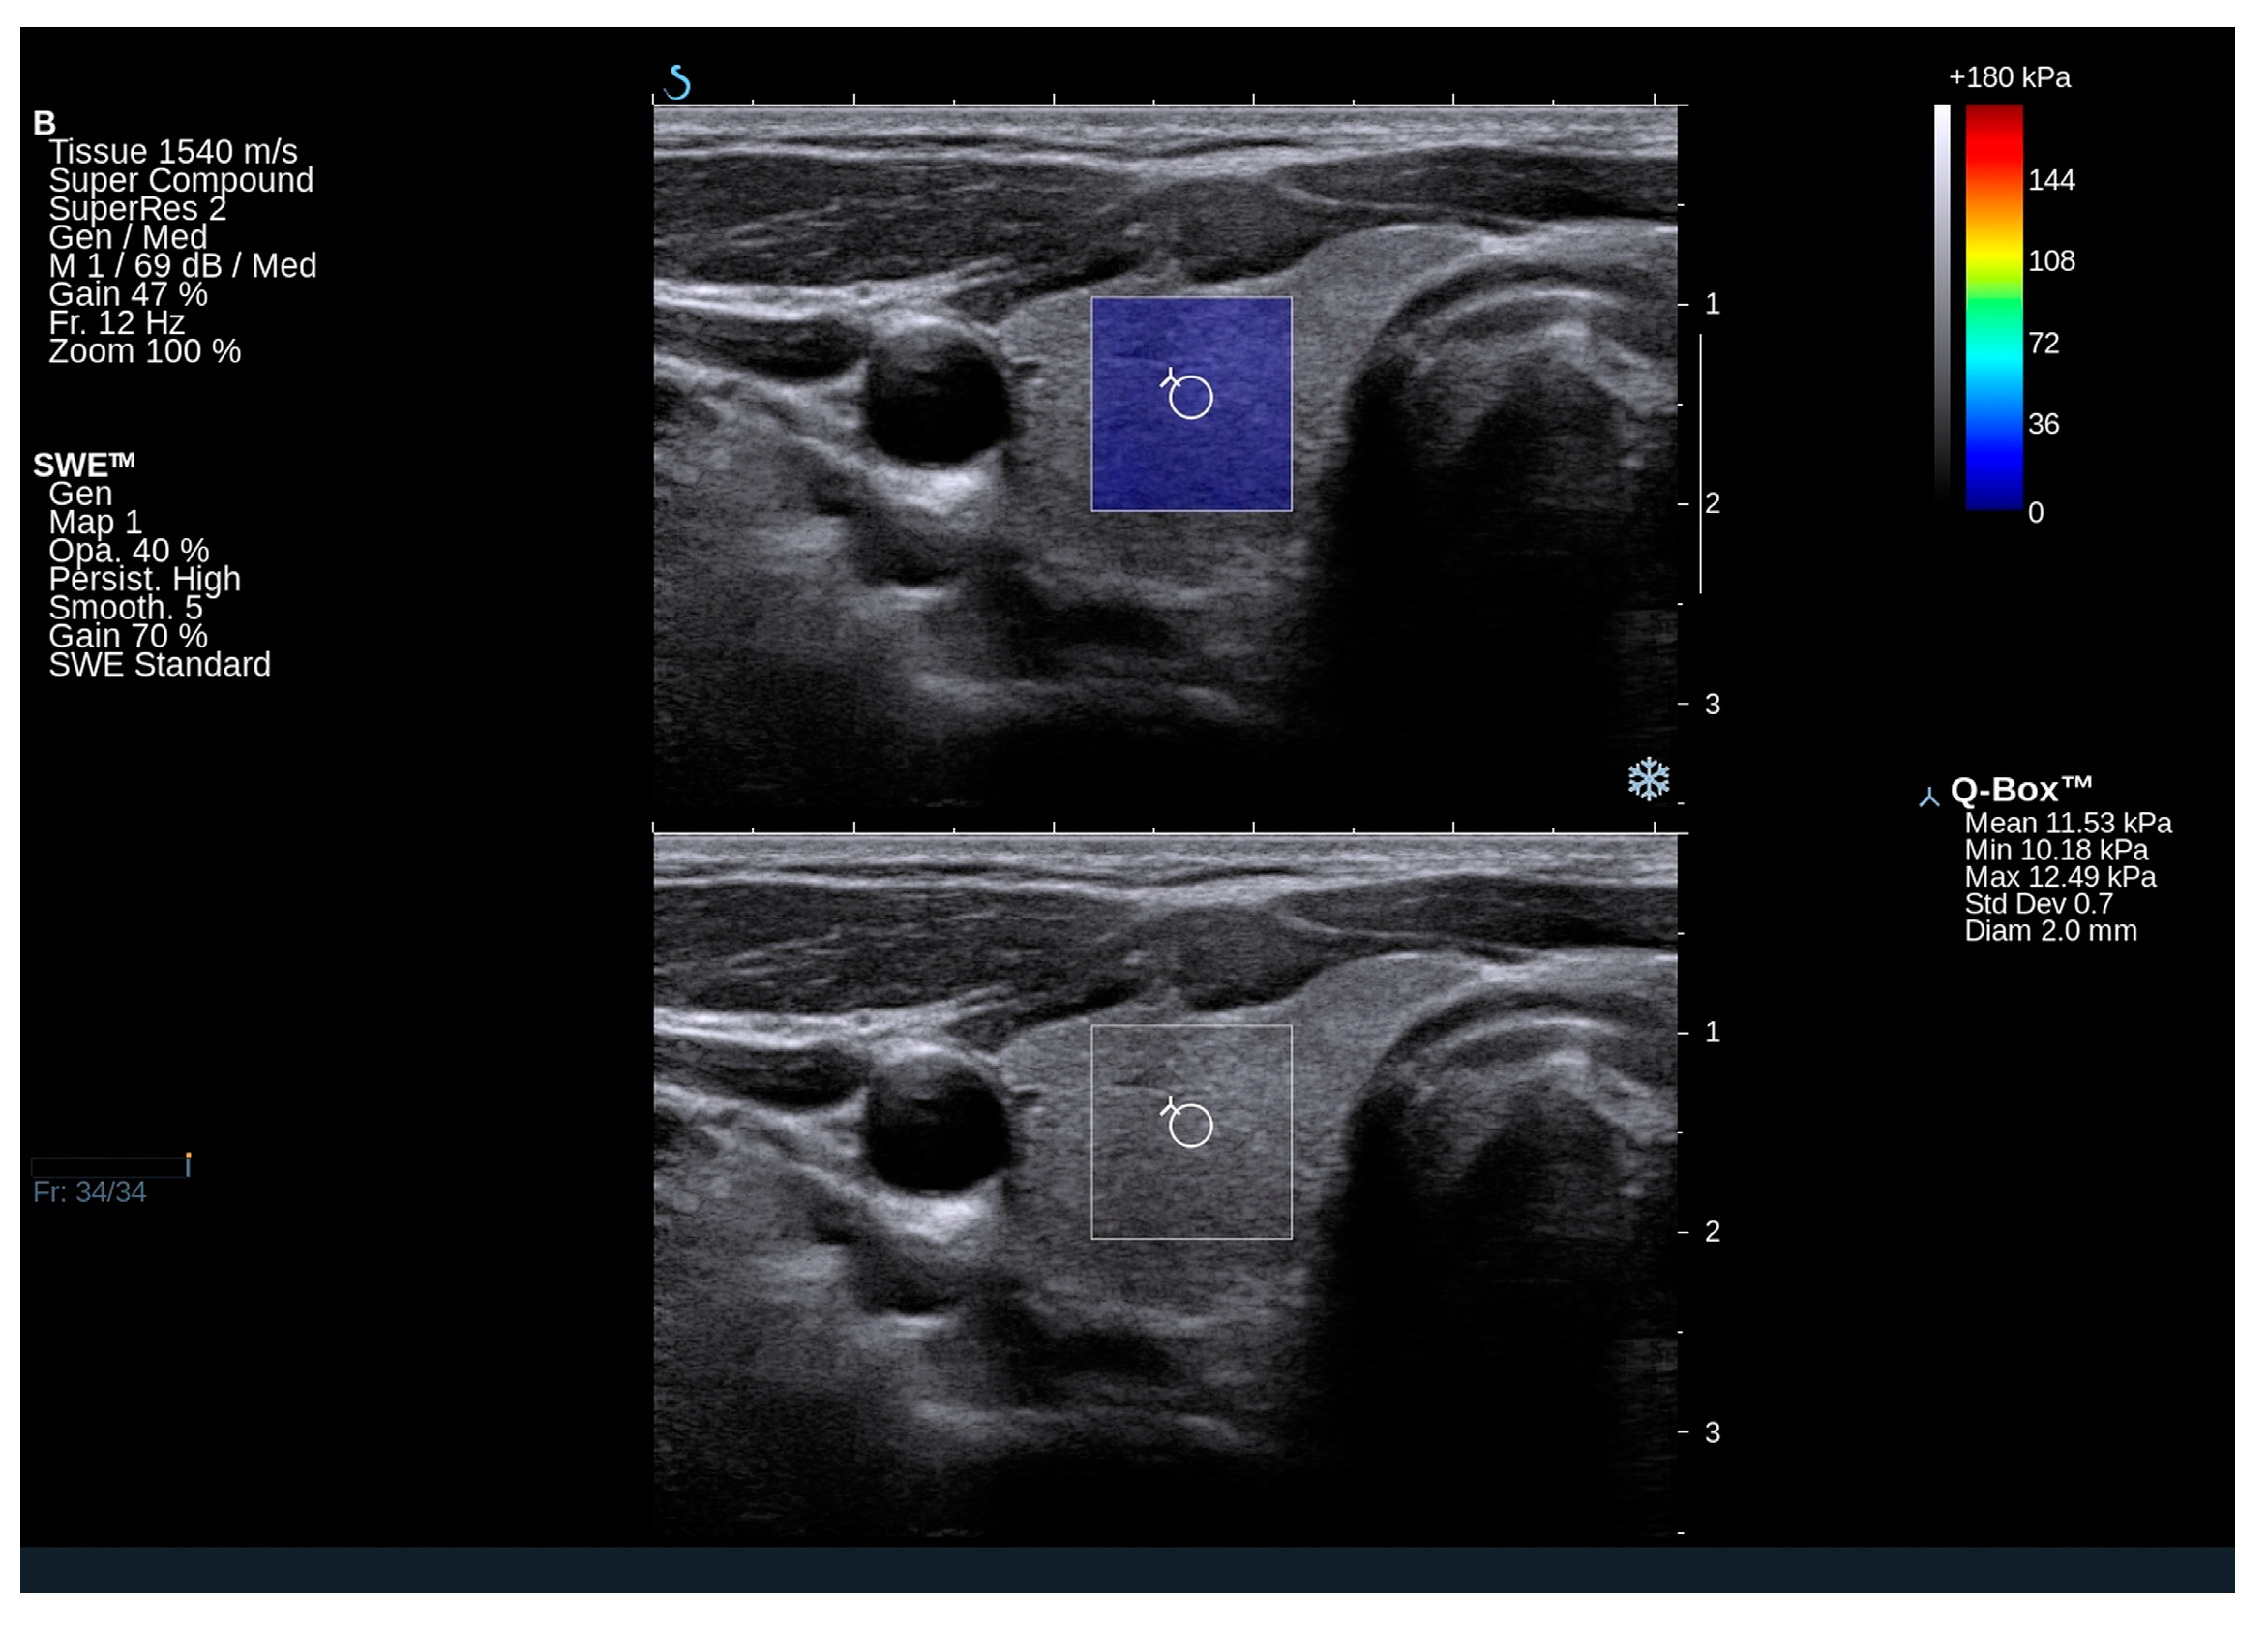

2.3. Elastography Results

4.2. Thyroid Ultrasound and Shear Wave Elastography (SWE)

| Right lobe Qbox mean (kPa) | 17.2 (11.9–20.9) | |

| Right lobe Qbox min (kPa) | 11.3 (6.8–13.3) | |

| Right lobe Qbox max (kPa) | 25.4 (18.8–31.5) | |

| Right SD | 3.5 (2.7–4.5) | |

| Left lobe Qbox mean (kPa) | 14.9 (11.3–21.5) | |

| Left lobe Qbox min (kPa) | 8.7 (5.3–12.5) | |

| Left lobe Qbox max (kPa) | 22.9 (17.3–29.6) | |

| Left SD | 3.2 (2.1–4.0) | |